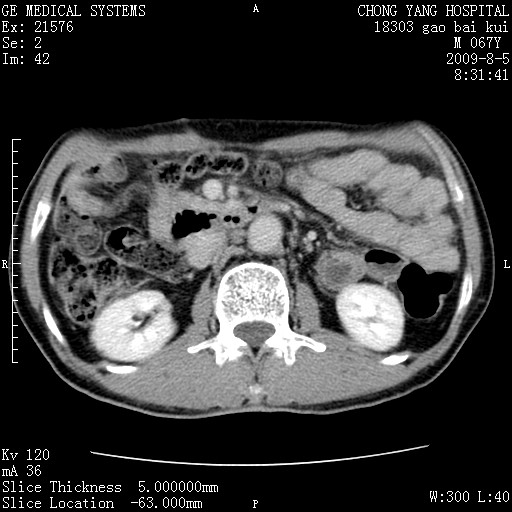

这个也过了,考虑胰腺钩突癌或壶腹癌,不除外胰管粘液乳头瘤伴胰管扩张,肝内胆管积气.

1)考虑胰头癌或壶腹癌并胰管扩张。2)肝外胆管扩张、积气,胆囊影未见;考虑术后改变。3)胃壁增厚?建议必要时行胃镜检查。

考虑胰头癌并十二指肠受侵。